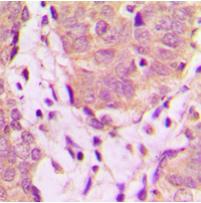

Immunohistochemical analysis of UBXN11 staining in human breast cancer formalin fixed paraffin embedded tissue section. The section was pre-treated using heat mediated antigen retrieval with sodium citrate buffer (pH 6.0). The section was then incubated with the antibody at room temperature and detected using an HRP conjugated compact polymer system. DAB was used as the chromogen. The section was then counterstained with haematoxylin and mounted with DPX.